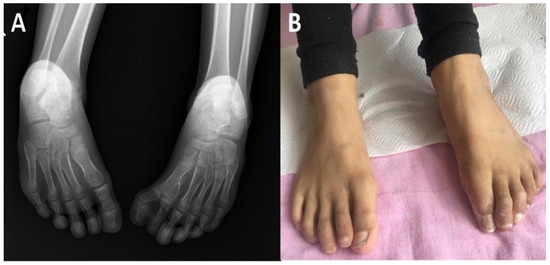

2. Clinical Report

2.1. A General Description of the Patients